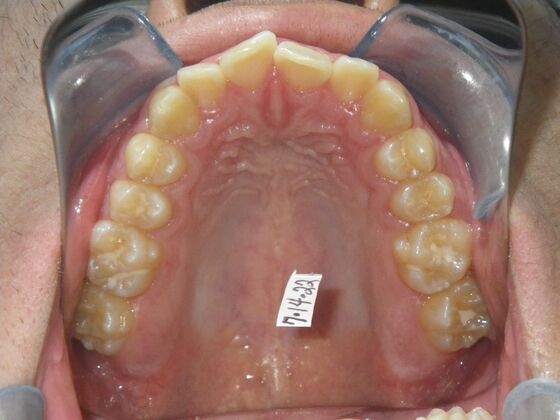

Patient presents with constricted upper and lower arches that will need expansion as well as slenderizing (IPR) to correct upper and lower anterior crowding.